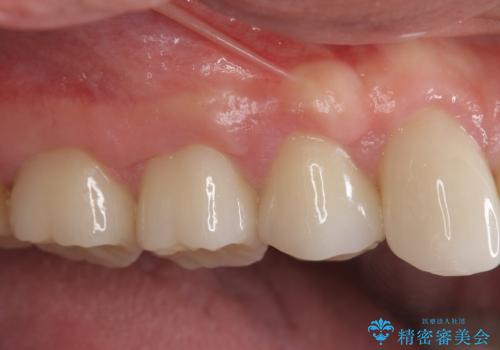

歯周外科で達成する安定したクラウン周囲の歯肉環境

すり減ってしまった歯に対し、歯冠長延長術(歯周外科)を行うことで安定したクラウンを製作・装着することが出来ました。